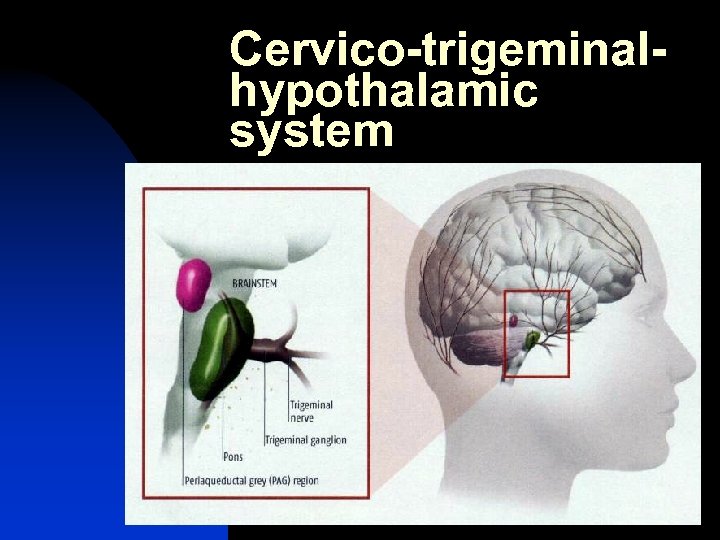

Cervico-trigeminalhypothalamic system

Cervico-trigeminalhypothalamic system